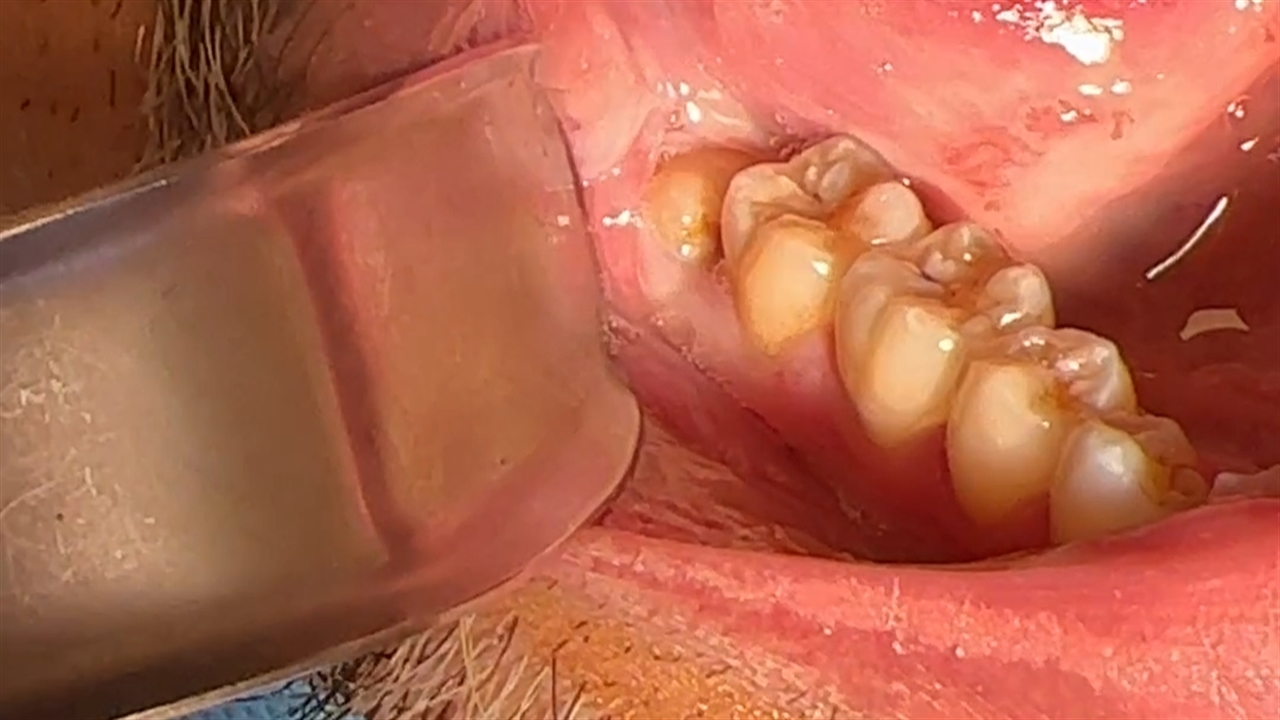

دندان عقل نیمه نهفته به حالتی گفته میشود که دندان عقل به طور ناقص از لثه بیرون میآید. در این وضعیت، بخشی از دندان قابل مشاهده است اما بخش دیگر زیر لثه باقی میماند. این حالت معمولاً باعث التهاب، درد، فشار به دندانهای مجاور و حتی عفونت میشود. علائمی مانند بوی بد دهان، درد در فک، لثه متورم یا خونریزی از علائم شایع این مشکل هستند. در چنین مواردی، جراحی دندان عقل نهفته و نیمه نهفته در جوانرود به عنوان یک راهکار قطعی، توصیه میشود.

ممکن است دندان عقل در دهان شما هیچ نشانهای نداشته باشد، اما در معاینات رادیولوژی مشخص شود که این دندان در زاویهای خطرناک رشد کرده و در آینده دردسرساز خواهد شد. زمانی که دندان عقل به صورت افقی یا زاویهدار در فک قرار گرفته باشد یا در حال فشار آوردن به دندان مجاور باشد، باید هرچه سریعتر برای جراحی اقدام کرد. اگر در جوانرود زندگی میکنید و این علائم را دارید، مراجعه به متخصص برای کشیدن دندان عقل در جوانرود امری ضروری است.

در مواردی که دندان عقل به صورت کامل از لثه بیرون زده و به راحتی قابل دسترسی باشد، میتوان آن را بدون نیاز به جراحی، کشید. اما در بیشتر موارد، به ویژه برای دندانهای نهفته یا نیمه نهفته، جراحی اجتنابناپذیر است. اگر به دنبال کشیدن دندان عقل در جوانرود بدون جراحی هستید، ابتدا باید از طریق عکسبرداری دقیق، وضعیت دندان شما مشخص شود.